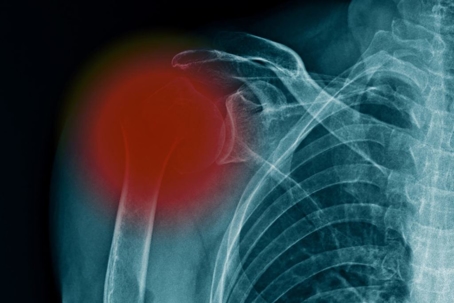

The victim was taken to nearby Glens Falls Hospital immediately following the accident and subsequently seen at Orthopedic Associates of Dutchess County, where an orthopedist diagnosed her with a 4-part comminuted fracture of the humerus, meaning the bone was splintered into four fragments. She was also diagnosed with nerve damage that caused pain, numbness, and tingling in the arm, likely a permanent condition. Due to the severity of her injuries, the orthopedist recommended the victim undergo a reverse total shoulder replacement, a costly and invasive procedure that involves replacing the bone with permanent hardware.